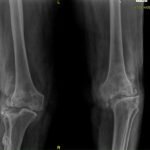

- Rheumatoid Arthritis: In this the joint lining (synovial membrane) that surrounds the joint becomes thickened and inflamed. If it is Chronic and not treated early with newer drugs can cause erosion of joint surfaces. This produces pain, swelling, stiffness and ultimately causing deformity like knock knee or bow legs.

- Osteotomy: If there is deformity of Bow legs or Knock knees in a younger person than corrective osteotomy to correct the alignment of the leg helps the knee pain.

In advanced stages of arthritis patient experiences pain on movement, disturbed sleep, stiffness, swelling and deformity. Sometimes pt needs walking stick and not relieved by non surgical treatment than total knee replacement is the operation of choice.